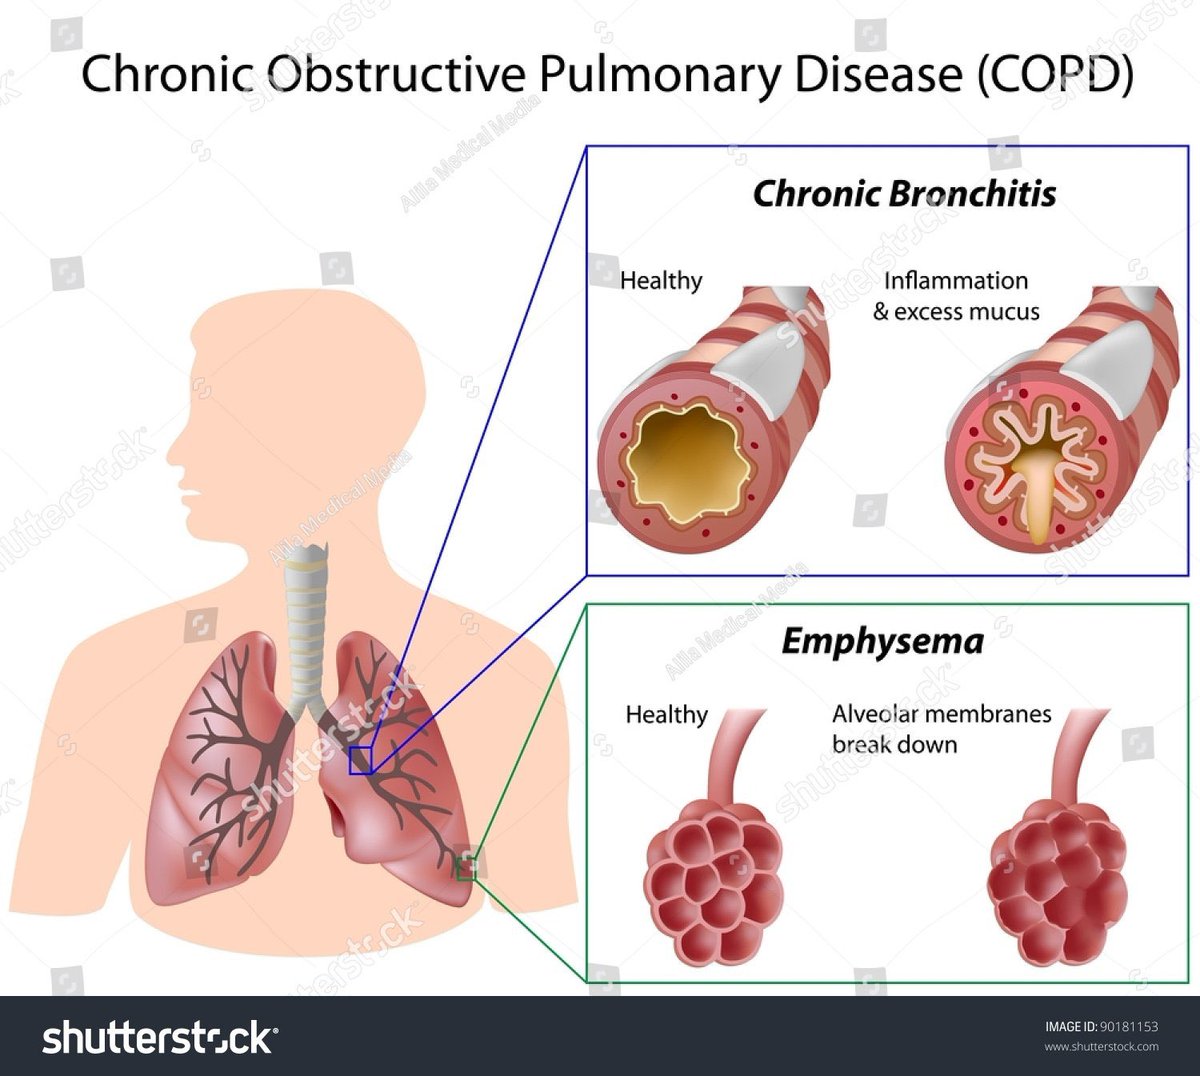

2_ايش الفرق بين asthma و copd ؟

2_ايش الفرق بين asthma و copd ؟